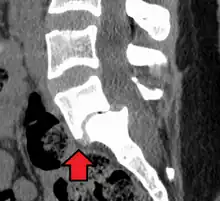

Degenerative spondylolisthesis at L5 - S1.

(A) CT sagittal view of a low grade slip.

(B) Lateral radiograph pre-operative intervention.

(C) Surgically treated with L5 – S1 decompression, instrumented fusion and placement of an interbody graft between L5 and S1.